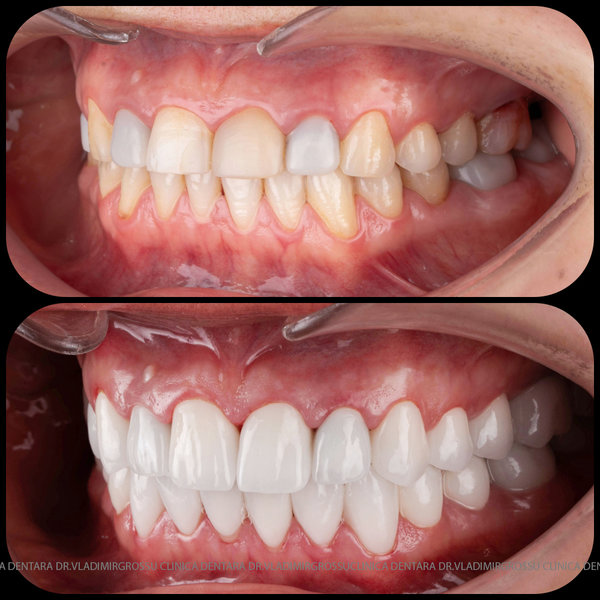

Caz 1

Transformările estetice și impactul reabilitării asupra vieții pacienților

Reabilitarea dentară produce o schimbare vizibilă și profundă în aspectul pacientului, cu efecte pozitive evidente asupra stimei de sine și a calității vieții. Mulți pacienți relatează bucuria redobândirii funcției masticatorii și dispariția complexelor legate de aspectul dentar.